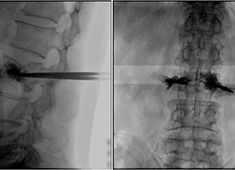

C臂機(jī)在打骨水泥時(shí)是怎么使用的(PKP手術(shù)記錄)

在打骨水泥時(shí)通常要借助C臂機(jī)來(lái)進(jìn)行,具體是如何使用的呢?下面通過(guò)南京醫(yī)科大學(xué)第二附屬醫(yī)院的一則手術(shù)案例來(lái)深入學(xué)習(xí)。首先將患者處于俯臥位,然后利用普愛(ài)大平板C臂機(jī)擺位靈活的特點(diǎn),快速定位椎弓根位置...